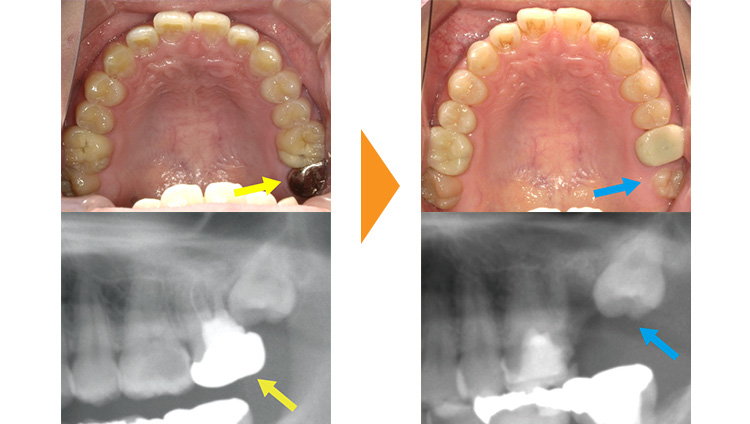

紹介元の歯医者さんで奥歯を抜歯しないといけないと言われた患者様です。予後不良の左上7を抜歯後、部分矯正にて左上8の牽引・排列を行った例となります。

左上7の状態が悪く抜歯適応です。(黄矢印)

左上7抜歯後、左上8が自然に生えてくるのを待ちました。(青矢印)

リンガルアーチとワイヤーを使用し、約9か月で排列しました。

矯正後、仮歯の修正をしていただき治療は終了となります。(赤矢印)

この方のように全体的な歯並びに問題はないものの、むし歯が原因で抜歯になってしまった場合に部分的な矯正治療が効果的な場合があります。

矯正治療にて本来であれば使えなかった親知らずを使用し、インプラントや入れ歯を回避することができました。

| 初診時 | 28歳男性 |

|---|---|

| 主訴 | 他院より紹介・インプラントの回避・親知らずの使用希望 |

| 期間 | 約9か月 |

| 矯正 | 部分矯正・ブラケット・ワイヤー・リンガルアーチ |

| 費用 | 基本検査22,000円・契約料275,000円・調整料5,500円/月(税込) |

| 治療上のリスク | 歯磨き不良の場合はむし歯になる可能性。 習癖に伴う後戻りの可能性。 |